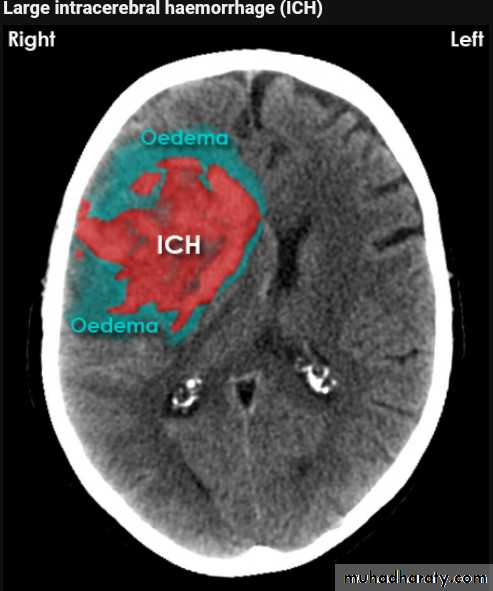

Acute Intra cerebral hematoma

CT finding :Hyper dense area , surrounded by edema , any where within the brain parenchyma.

Shifting of the midline

Compression of the ipsi lateral ventricle .

Associated with infarction , # , trauma concussion , tumor …..